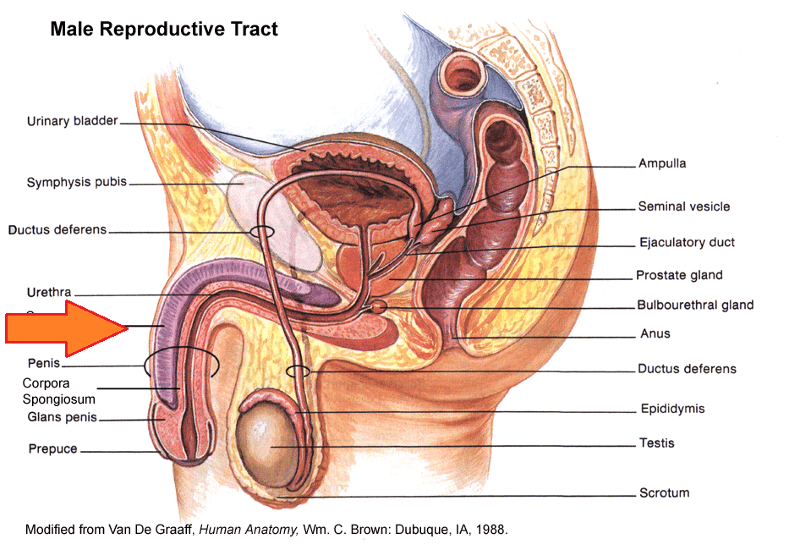

Anus

Bulbourethral gland (male)

Ejaculatory Duct

Epididymis

External urethral orifice (male)

Glans penis

Prostate gland

Scrotum

Seminal vesicle

Testis (s.) Testes (pl.)

Vas deferens (=ductus deferens)